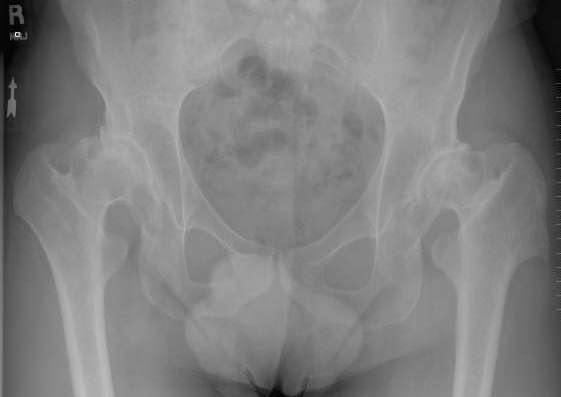

Andre Bilateral ASR July 31, 2009 Dr. Scott Ball

39 year old male with Hip Arthirtis since age 14